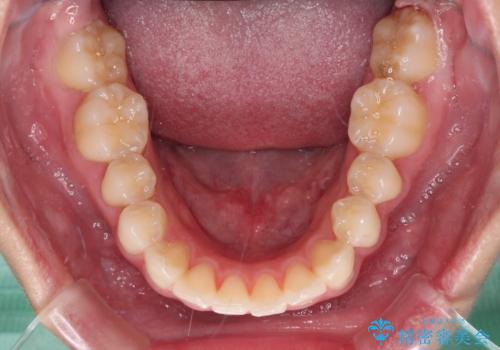

クロスバイト改善中には歯髄壊死を起こすリスクがあるため、神経に問題がないか確認しながら治療を進めて行く必要があります。

思っていたよりも早くクロスバイトは改善され、歯髄壊死に至ることなく、無事に治療を終えることができました。